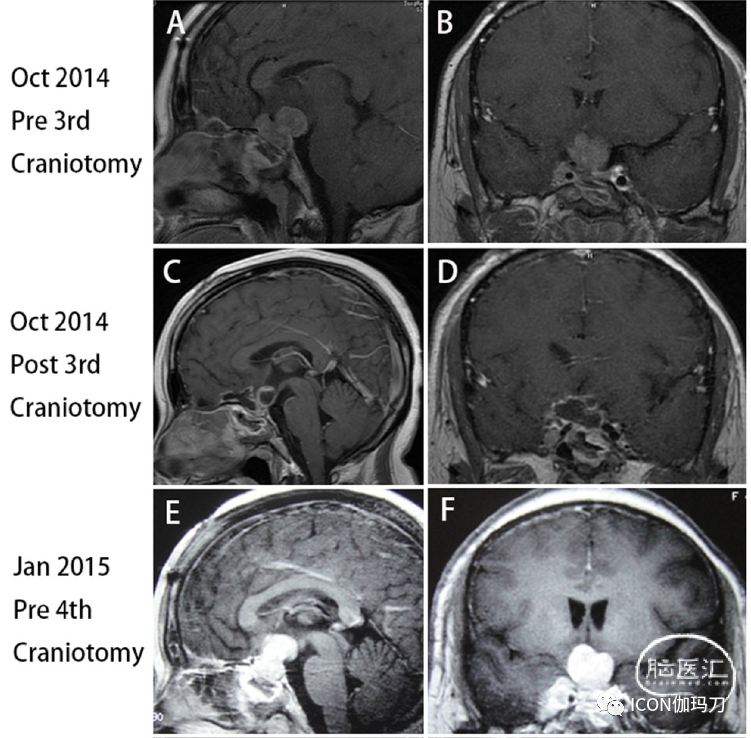

34岁女性,2009年12月因头痛、闭经和溢乳入院。原始血清泌乳素水平为700.0 ng/mL(补充图1),MRI显示2.x2.0 cm垂体大腺瘤,侵袭右侧海绵窦,完全包裹右侧颈内动脉(ICA) (Knosp分级4级)(图1A和B)。然后行经蝶窦手术(TSS),行全切除术(图1C和D)。根据病理报告诊断为泌乳素瘤,Ki-67标记指数(LI)为3%。但病理切片无法从其他医院获得。术后头痛、闭经、溢乳等症状明显改善,泌乳素水平降至正常范围(补充图1)。术后垂体激素水平基本正常。在术后随访中,患者出现急性右侧视力下降,MRI报告肿瘤迅速扩大并压迫视交叉(图1E和F),血清逆乳素水平再次上升至356.0 ng/mL(补充图1)。2011年10月,患者首次行额部开颅手术。肿瘤亚全切除(图1G和H),术后视力减退症状明显改善,血清泌乳素水平降至356.0 ng/mL(补充图1)。术后患者给予醋酸去氨加压素0.1 mg/d治疗尿崩症。垂体前叶功能基本正常。不幸的是,她又出现视力丧失,2012年3月和磁共振表明快速增长的肿瘤压迫视交叉和侵袭第三脑室(图1 I和J)和血清泌乳素水平增加到200.0 ng / mL(样本不稀释)又(补充图。1)。她接受了第二次经额开颅术后,视力减退症状明显改善,血清泌乳素水平再次降至37.0 ng/mL(补充图1)。然而,实验室结果显示血清皮质醇水平下降0.08 μg/dl(参考文献:5.7 -22.6 μg/dl), GH水平0.01 μg/L(参考值:1- 4,6 μg/L),总T4水平30.21 nmol/L(参考值:75-150 nmol/L),游离T4水平4.07 pmol/L(参考值:7.5-15 pmol/L)。患者给予醋酸强的松30 mg /天,左旋甲状腺素钠100 μg /天,垂体前叶激素水平基本恢复正常。从那以后,她接受了永久性的激素替代疗法。

图1.术前矢状位(A)和冠状位(B)磁共振成像(MRI)显示垂体大腺瘤2.5厘米* 2.0厘米,侵袭海绵窦,完全包裹右侧颈内动脉(ICA)(Knosp4级)。(C)和(D)三个月后第一次蝶手术(TSS),MRI显示肿瘤被完全切除。(E)和(F)在第一次经额开颅前,2011年10月MRI显示一个迅速扩大的肿瘤,并压迫视交叉。(G)和(H)第一次经额开颅后,MRI显示肿瘤近全切除。(I)和(J)第二次开颅前,2012年3月MRI显示肿瘤快速生长,视神经视交叉受压,侵袭第三脑室。(K)、(L)第二次经额开颅后,肿瘤次全切除。